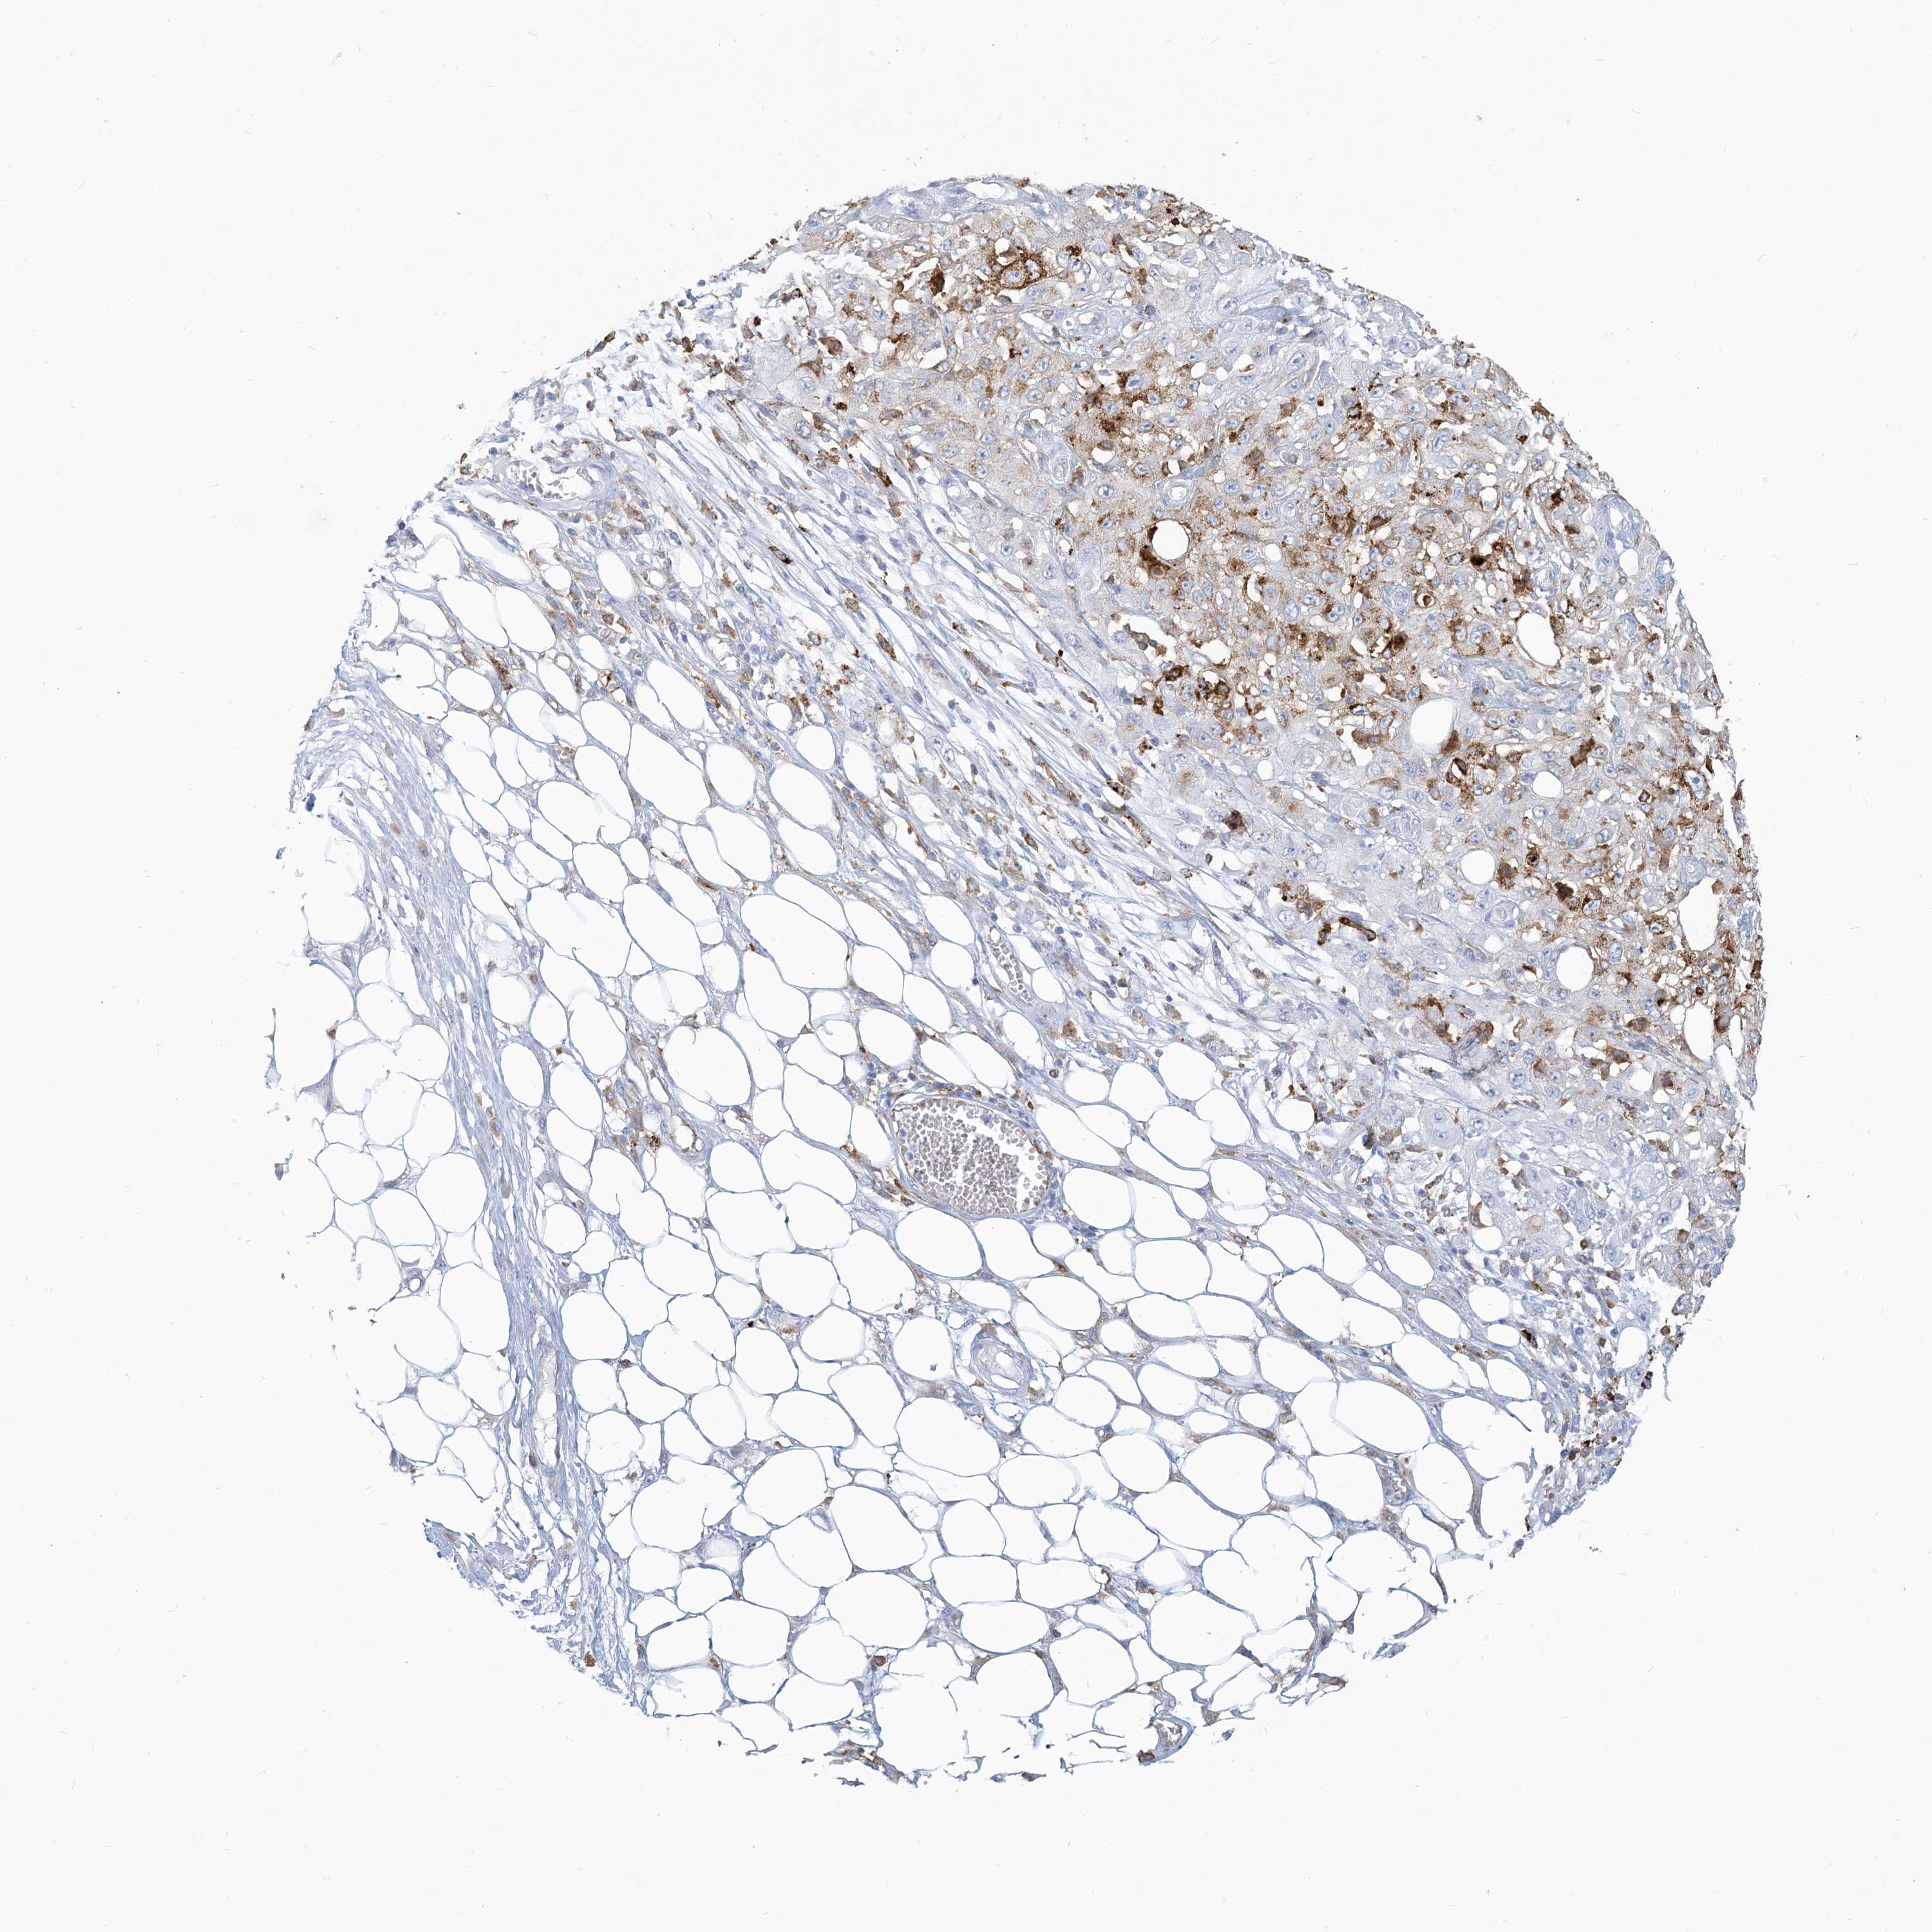

CANCER SKIN CANCER Show tissue menu

SKIN CANCER - Protein expressioni

A mouse-over function shows sample information and annotation data. Click on an image to view it in a full screen mode. Samples can be filtered based on level of antibody staining by selecting one or several of the following categories: high, medium, low and not detected. The assay and annotation is described here.

Antibody staining in the annotated cell types in the current human tissue is reported as not detected, low, medium, or high, based on conventional immunohistochemistry profiling in selected tissues. This score is based on the combination of the staining intensity and fraction of stained cells.

Each image is clickable and will lead to virtual microscopy that enables deeper exploration of all samples and also displays staining intensity scores, fraction scores and subcellular localization as well as patient and tissue information for each sample.

Basal cell carcinoma

Squamous cell carcinoma, NOS

Squamous cell carcinoma, metastatic, NOS

Squamous cell carcinoma in situ, NOS

Adnexal tumor, benign